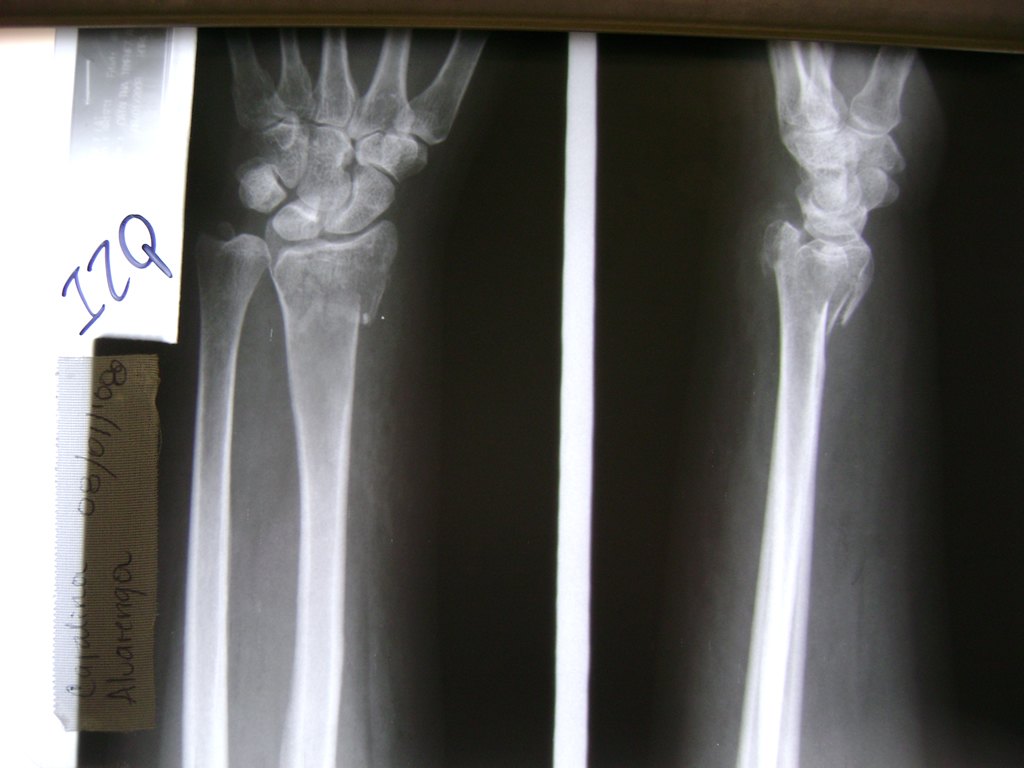

Cirugías de Codo - Cirugías de Muñecas y Manos

Los procedimientos más comunes en cirugía de la mano son aquellos destinados a reparar traumatismos, incluyendo lesiones de tendones, nervios, vasos sanguíneos, y articulaciones; huesos fracturados; y quemaduras, cortes, y otros daños de la piel.